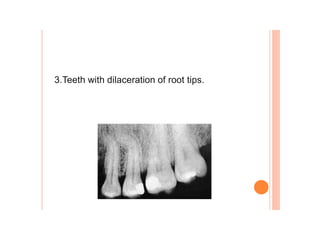

Dental caries, also known as tooth decay, is caused by certain types of acid-producing bacteria in the mouth that damage tooth structures when fermentable carbohydrates like sugar are present. It can lead to pain, tooth loss, infection, and in severe cases, death. While early signs may include white spots on teeth, untreated caries will form cavities. Risk factors include poor oral hygiene, frequent sugar consumption, dry mouth, and tobacco use. Treatment involves removing decay, restoring teeth, or extracting severely damaged teeth to prevent further destruction and infection. Preventive measures include proper brushing, flossing, limiting sugar intake, dental sealants, and fluoride therapy.